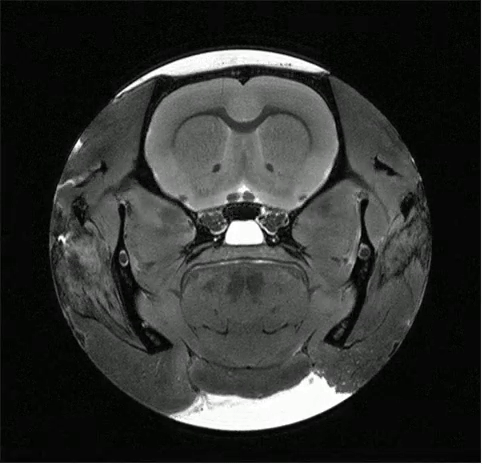

null Bruker 7T MRI BioSpec 70/30 USR

| The 7T MRI scanner allows for high-resolution structural, functional, and molecular in vivo and ex vivo MR imaging. |